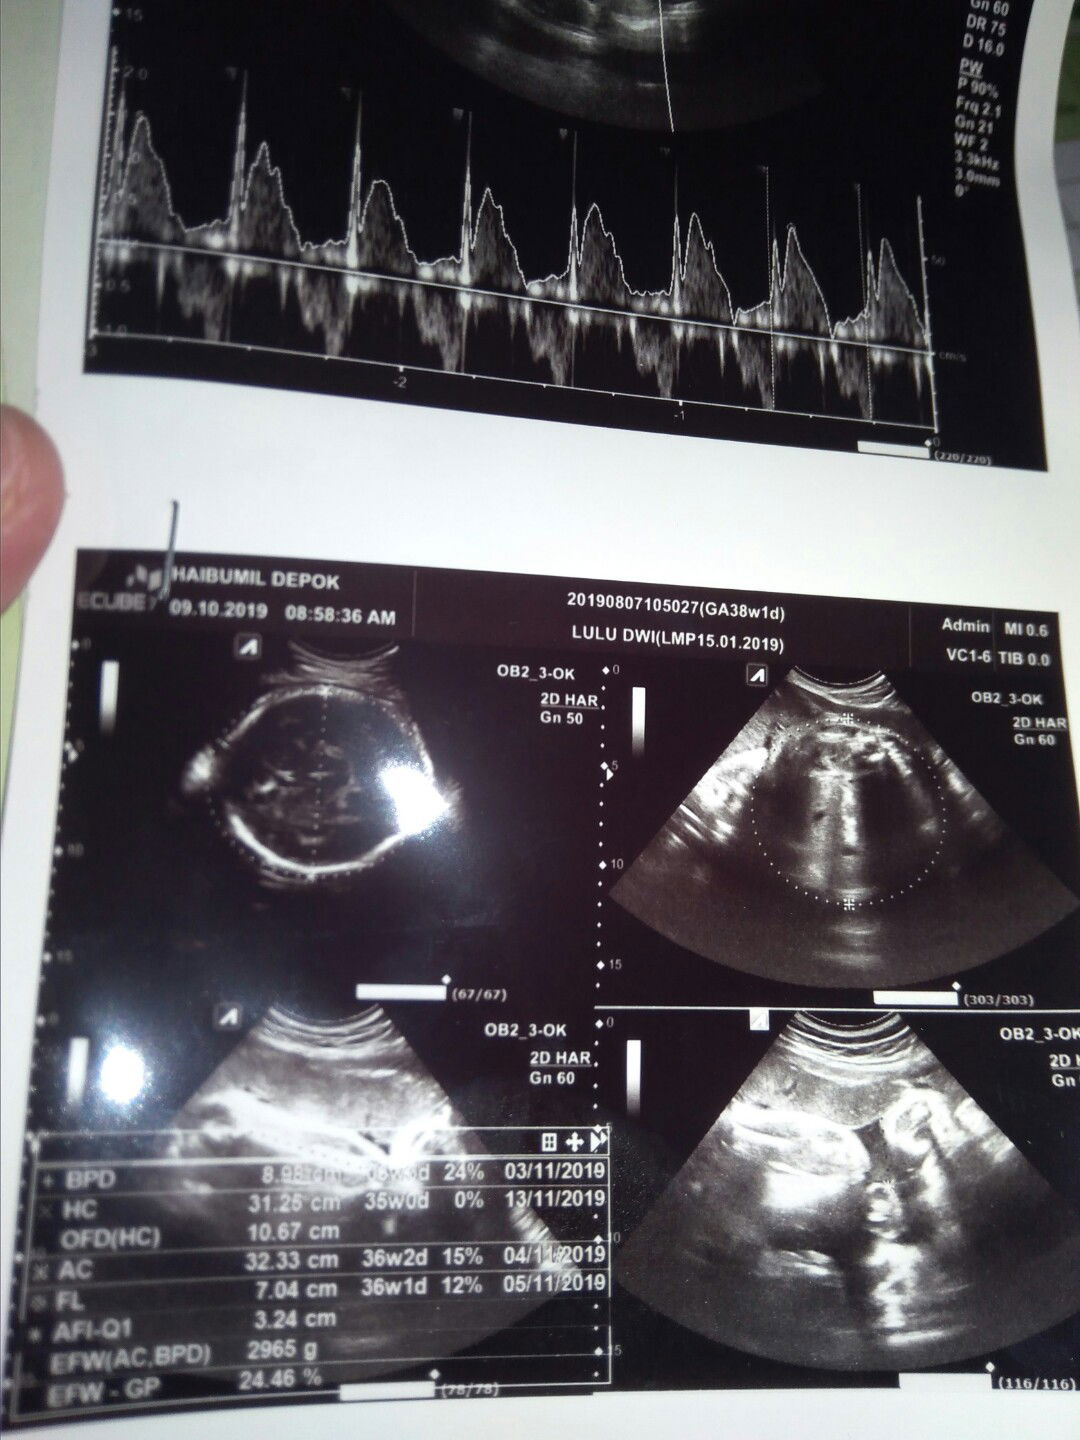

Maaf mau tanya disini adakah yg paham ini janin saya usia nya 36w1d kan yah? Mohon bantuan nya ya bun..